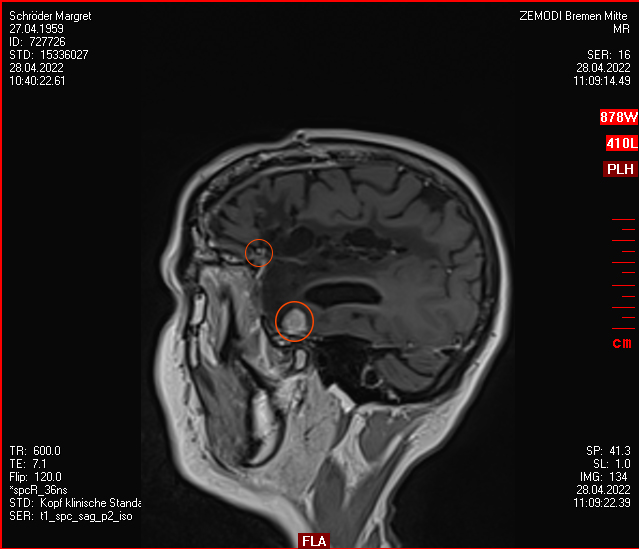

Am 03. November war mein Kontrollbesuch beim MRT. Leider ist ein kleiner Befund aufgetaucht. Schau das Video, dann kannst Du sehen.

Nun kann sich zeigen, ob die menschliche Medizin eine Lösung für mich hat. Möglichkeiten gibt es. Sogar mindestens eine, die der Neurochirurg als fein und elegant beschreibt. Gamma-Knife, eine Strahlentherapie. Klingt etwas nach Star Wars – man wird sehen,  etwas abwarten ist auch drin.

Heute war ich im MRT im Bremen. Der Befund des auswertenden Arztes ist, dass er der Meinung ist, dass der Tumor etwas gewachsen ist. Ich habe mir die Bilder angesehen und versucht diese Aussage zu verstehen. Vermutlich ist sie richtig, aber das Wachstum ist nicht heftig nur vielleicht von 0,7 cm auf 0,8 cm. Aber Gamma-Knife hat es offensichtlich nicht entfernt.

Zu meinem Geburtstag am 27.4. habe ich sehr schöne Geschenke bekommen und kann mich auch über meinen bunten Garten freuen, im Herbst gab es ein Tulpen-Sonderangebot, dem konnte ich nicht wiederstehen! Und nun ist das Ergebnis zu sehen. Am 28. April war wieder mal MRT-Termin. Leider hat es an dem Tag eine Vertretung des auswertenden Arztes gegeben, die Ärztin war super freundlich aber hat keine ganz konkreten Aussagen machen können, aber sie hat mir 2 CDs gebrannt, ich konnte eine gleich bei den Neurochirurgischen Ambulanz abgeben und eine mit nach Hause nehmen. Mein Blick auf die Bilder hat eine nazu unveränderte Lage gezeigt.

Heute war der Termin beim Chirurgen, leider schon um 9:00 Uhr und natürlich wollte ich die knapp 20 km mit dem Rad zurück legen, Stephan wollte gerne mitkommen. Leider war die bereits abgegebenen CD nicht eingelesen worden und so musste erstmal die Datenverarbeitung arbeiten und wir warten, bis wir eine Auskunft bekommen konnten. Fazit: Der bestehende Tumor ist kaum gewachsen. Aber es hat sich leider ein 2. Fund ergeben, sehr klein aber deutlich sichtbar. Aber Maßnahmen sind erstmal nicht notwendig.